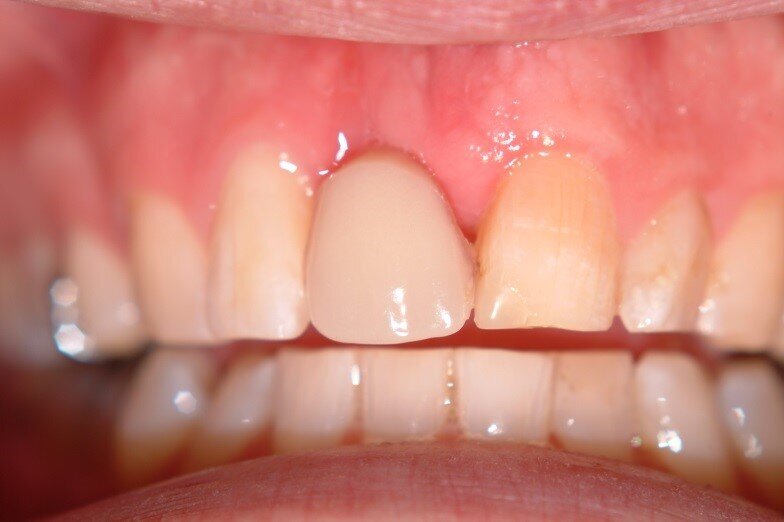

Patient RR was a healthy non-smoking 44 year old male who presented with a complaint of an unaesthetic upper right central incisor with extensive recession showing a large amount of darkened labial root surface. The situation was worsened by a high smile line and a porcelain crown contrasting dramatically with the root colour. He had had periodic swelling at the apical part of the recession over a long period. There was a history of trauma in his teens leading to root canal treatment and a crown, and subsequent apicectomy in his 20s. Clinical examination revealed an otherwise periodontally healthy, well looked-after mouth. (Fig. 1, 2, 3)